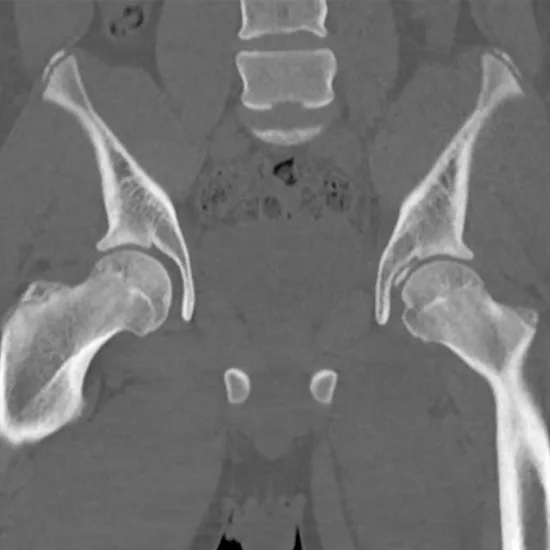

CECT (Contrast Enhanced Computed Tomography) of the Left Hip Joint is an imaging test that is used to diagnose problems in the left hip region.  For this scan, a series of x-rays and a special dye is used to highlight the region that doctor wants to examine and to obtain a clear picture of the left hip joint.

CECT Left Hip Joint is called the Contrast-Enhanced Computed Tomography scans of the Left Hip Joint region. This imaging test creates a three-dimensional scan image of the Left Hip Joint region using a special dye and radiations.

Most commonly a CECT scan for the hip joint are done to assess the structures of the hip joint including the articular cartilage, the scan can be used to visualise and diagnose labral tears in cases where the MRI is contraindicated